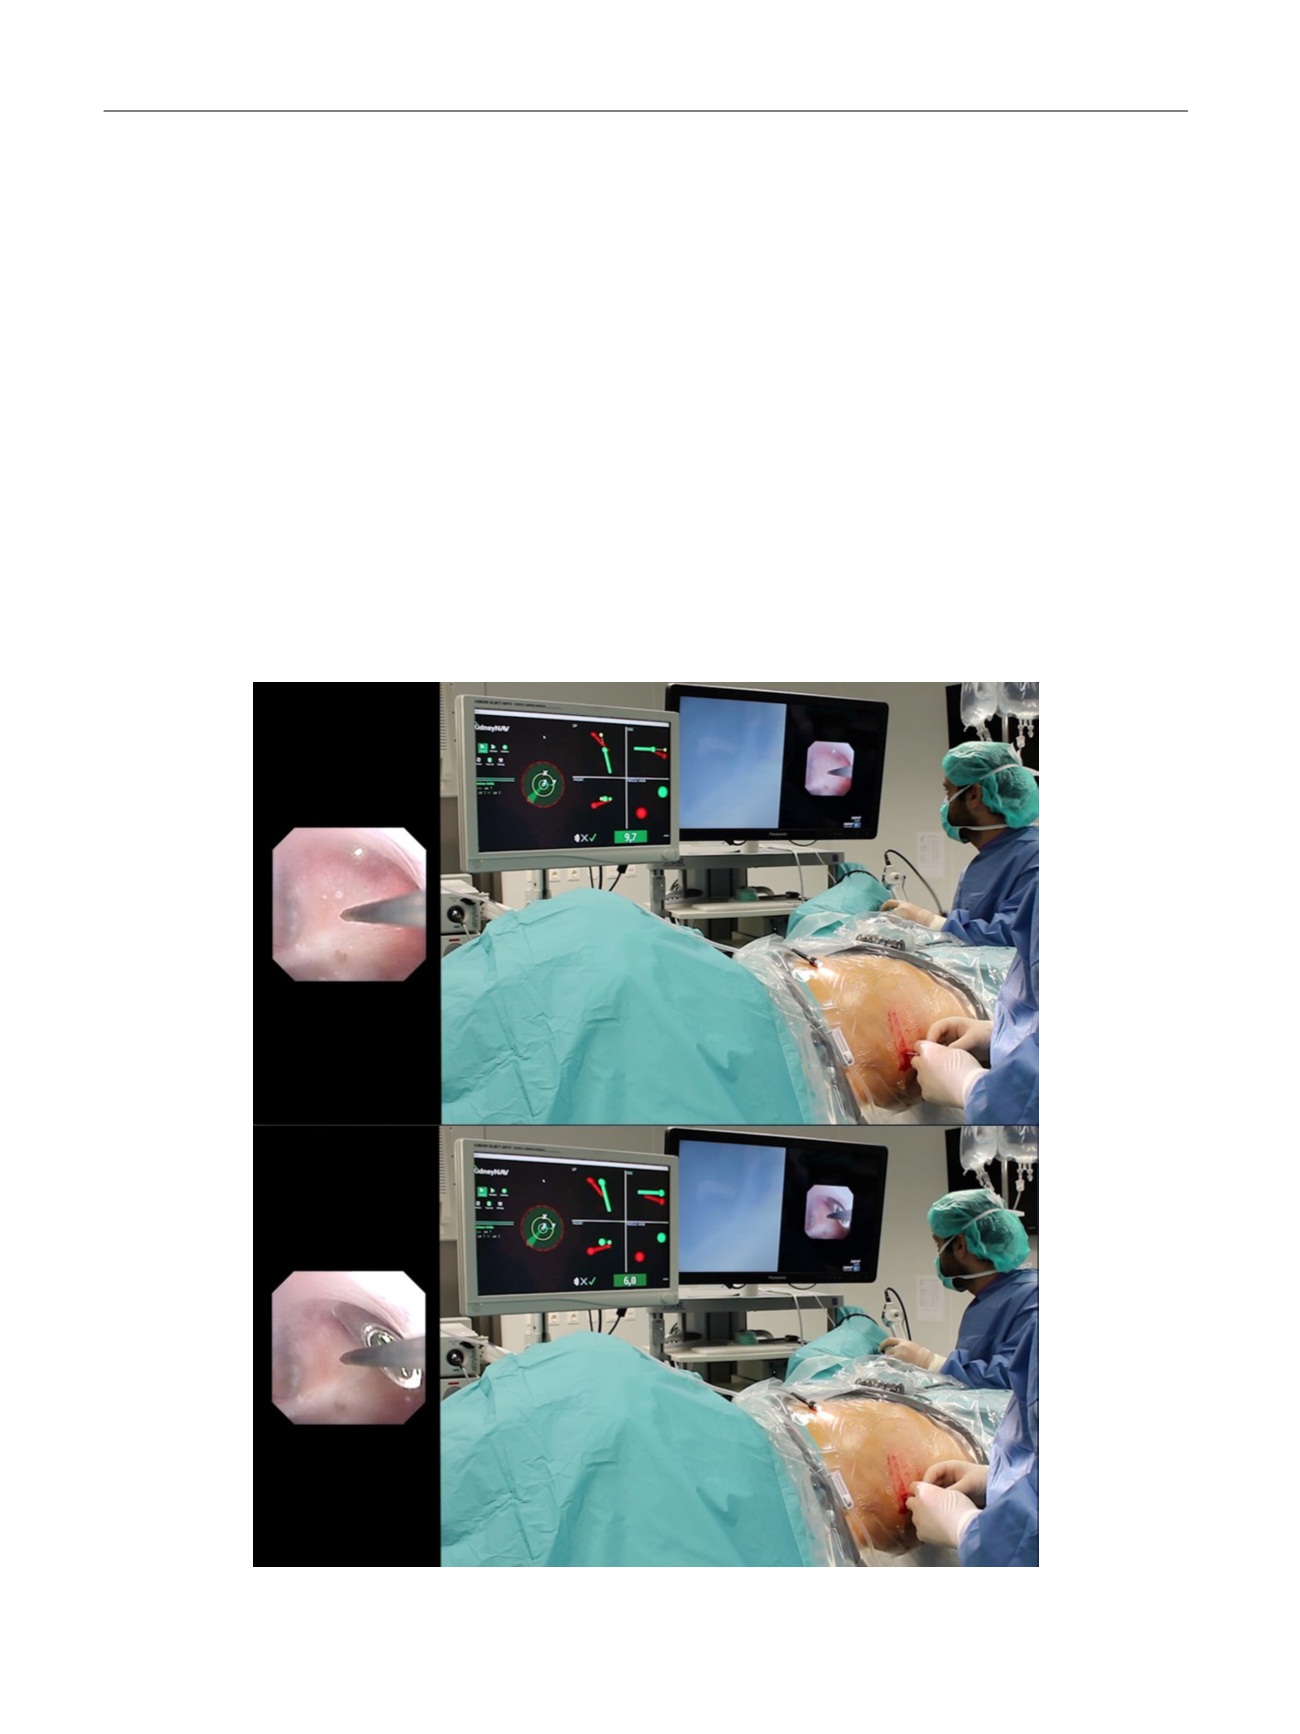

enoscope. Under ureteroscopy visualization, the surgeon selects the

ideal calyx for percutaneous access, and places the ureteral catheter with

the electromagnetic sensor in the fornix of the calyx.

An ultrasound scan is used to verify that the renal puncture track is

not obstructed by any unintended anatomical structure. The selected

calyx is punctured using an 18G needle with an electromagnetic sensor

on the tip of the stylet. The access is guided in real time by images

observed on the monitor

( Fig. 2). Once the needle tip is inserted into the

desired calyx the proper calyceal access is confirmed ureteroscopically,

and minor adjustments are made under endoscopic visualization.

Fig. 2 – Guided by the three-dimensional navigation software on the monitor and confirmed simultaneously by ureterorenoscope images, the surgeon

performs puncture of the lower calyx during human percutaneous nephrolithotomy.